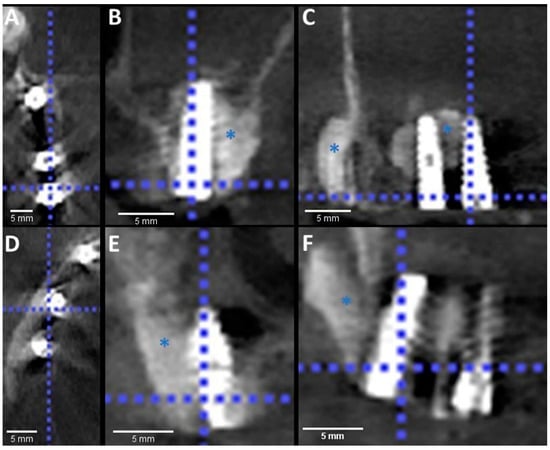

3. Results